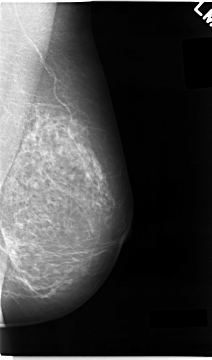

C_0043_1.RIGHT_MLO

C_0043_1.LEFT_MLO

C_0043_1.RIGHT_CC

C_0043_1.LEFT_CC

LEFT_CC LINES 4696 PIXELS_PER_LINE 2672 BITS_PER_PIXEL 12 RESOLUTION 50 NON_OVERLAY

LEFT_MLO LINES 4672 PIXELS_PER_LINE 2744 BITS_PER_PIXEL 12 RESOLUTION 50 NON_OVERLAY

RIGHT_CC LINES 4672 PIXELS_PER_LINE 2776 BITS_PER_PIXEL 12 RESOLUTION 50 OVERLAY

RIGHT_MLO LINES 4712 PIXELS_PER_LINE 2776 BITS_PER_PIXEL 12 RESOLUTION 50 OVERLAY